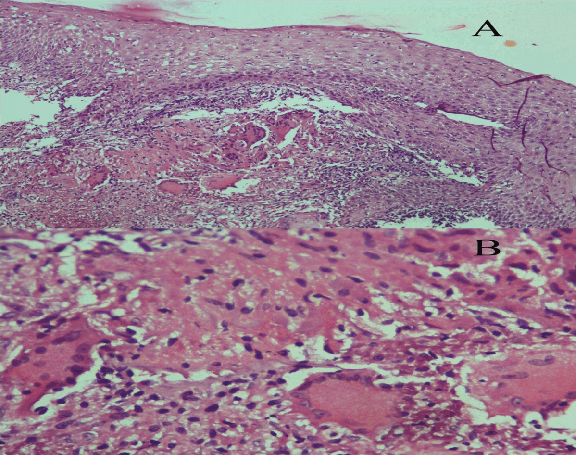

On local examination, indirect laryngoscopic examination showed a growth involving the supraglottis. There were no palpable lymph nodes in the neck. Examination of the ears and nose with para nasal sinuses (PNS) did not reveal any abnormality. In the routine examination of blood, hemoglobin estimation was 8.7 g/dL, erythrocyte sedimentation rate of 15 mm was seen at the end of first hour (AEFH). Total leucocyte count of 8600 per high powered field and differential leukocyte count of neutrophils 60%, lymphocytes 30%, monocyte 8% and eosinophil count of 2% was seen. Liver function tests were normal. Chest X-ray posterior anterior view showed normal lung fields. Direct fiberoptic laryngoscopy examination showed a polypoidal growth with hyperemia involving the epiglottis and bilateral aryepiglottic folds. (Figure 1) Bilateral vocal cord mobility was normal. Multiple punch biopsies were taken from the polypoidal growth. Ultrasonography of the abdomen did not reveal any findings suggestive of abdominal tubercular lesion. Serological test for human immunodeficiency virus was non reactive. The histopathological examination showed features of necrotizing inflammatory infiltrate lined by hyperplastic squamous epithelium and epithelioid granuloma with Langhan’s giant cells. (Figure 2A–B) Ziehl–Neelsen staining on the tissue section showed the presence of scanty acid-fast bacilli. Fiberoptic bronchoscopy was done for collection of bronchioalveolar lavage (BAL) fluid and examination for acid-fast bacilli. On microscopic examination of the bronchioalveolar lavage fluid, acid-fast bacilli were not seen by Ziehl–Neelsen staining. The diagnosis of primary laryngeal tuberculosis was confirmed. The patient was treated with anti-tubercular therapy for six months.

Cursor on image to zoom/Click text to open image

Figure 2: (A) Photomicrograph showing hyperplastic squamous epithelium with underlying epithelioid granuloma with Langhans giant cells and scanty necrosis (H&E stain, x10), (B) Photomicrograph showing an epithelioid granuloma containing Langhan’s giant cells (H&E stain, x40).